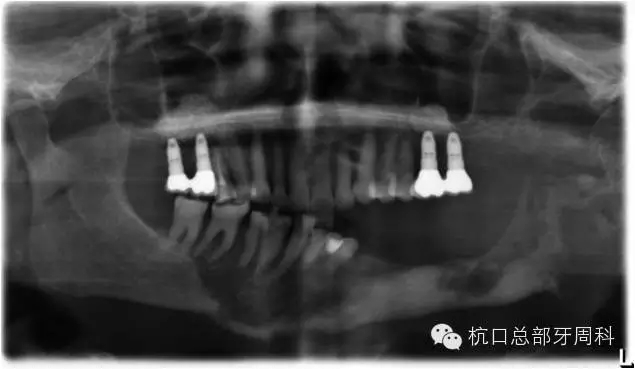

被診斷為種周炎時(shí)全景片  2011

111.webp.jpg